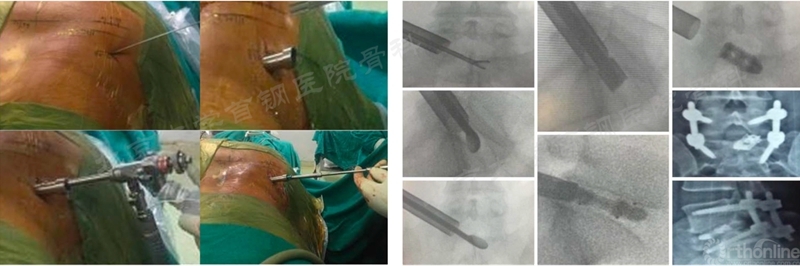

就在Min Seok Kang教授发表BE-EFLIF论文的半年之后,Dong Hwa Heo教授在这基础上进行两个改进,一是将通道切口重新确定在椎弓根外缘,二是关节突关节完全切除以便植入了更大的OLIF cage,Heo将这种手术方式命名为“改良远外侧内镜下椎间融合术”(Modified far lateral endoscopic transforaminal lumbar interbody fusion)。

一年后Jin Hwa Eum教授发表了该手术的系列病例并首次将这种术式命名为Ex TLIF,他在文中指出其最大的特征就是在BE-TLIF操作的基础上植入更大的Cage,植入Cage的路径是经过Kambin三角的,需要术中测量Kambin三角的底边长度,这一点与BE-TLIF是完全不同的(如图17)。

图17 Ex TLIF与Kambin三角底边长度及术后照片(照片来源于文献)

Ex TLIF这一名词是在双通道内镜手术下第一次被提出来的,是专属于双通道的一种融合技术。其沿用了BE-TLIF的部分手术技术,同时吸收BE-EFLIF中大cage斜插横置技术,具有十分广阔的应用价值和前景,是双通道下新融合方式的代表。